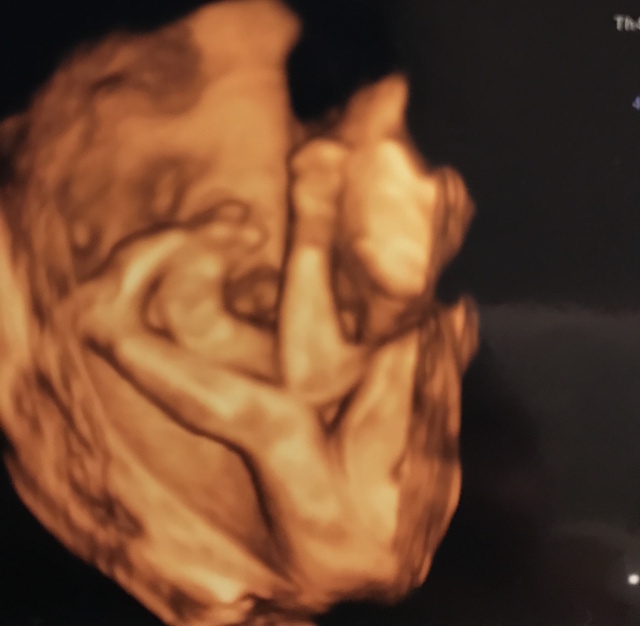

22週0日(22w0d・女の子)|kanahana さん(28歳)

エコー写真撮影時のエピソード:

記念に4Dエコーをしてもらいました。いつも顔の近くに手があって、顔が上手く写らない事が多かったけど、このエコー写真はたまたまタイミング良く顔が撮れて良かったです。

値段は5000円と高かったけど、いい記念になったのて、やって良かったと思ってます。